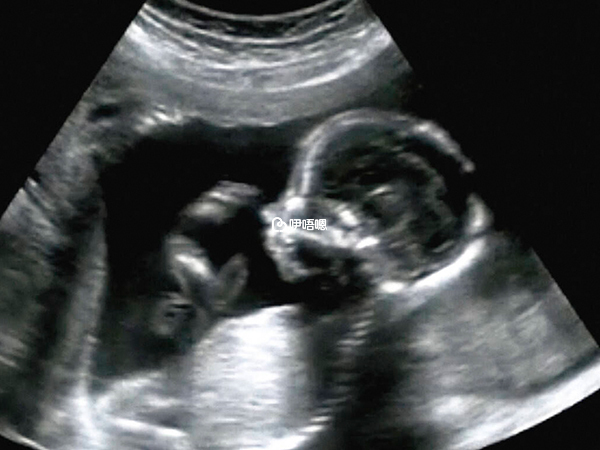

四維彩超主要是檢查胎兒是否面部畸形,還可以進行脊柱畸形篩查,檢查胎兒神經系統,生殖泌尿系統,消化系統等,四維雖然能看見寶寶的臉,但並不能完全肯定寶寶性別,為了滿足準媽媽好奇心,分享四維照片看男女方法:

看四維彩超單子,必須是照到胎兒寶寶的下半身,如果彩超影象有突出的東西,像一團菌狀,有時候可能出現3個亮點,那代表可能懷男孩,如果彩超影象有三條線的標誌,那代表可能懷女孩,這個方法和看影象一樣,都不是特別準確。

做四維拍到寶寶的面部輪廓還是比較清晰的,如果拍到具有性別特徵的部位那就更能明確胎兒性別了,但是大部分拍到的四維照片,都會對胎兒性別特徵進行隱藏,醫生也不允許告知家屬胎兒性別,一般生兒子的四維彩超圖片可能會有所不同。

如果做四維剛好從下往上拍到寶寶生殖器官的部位,那麼彩超影象上有三條線的標誌,代表可能懷女孩,如果彩超影象上有三個亮點,那麼代表可能懷男孩。

四維彩超能確定胎兒的性別,如果寶寶四維能看到生殖器,或者是面相很像男孩,那八九不離十就是男寶寶了,但是四維檢查也同樣需要胎兒配合才行,如果胎兒位置好,能夠看得清楚一點,那麼判斷懷男孩女孩的準確率會比較高,如果胎兒位置不好,有時候看不清楚,那麼判斷胎兒性別準確率也就不高。